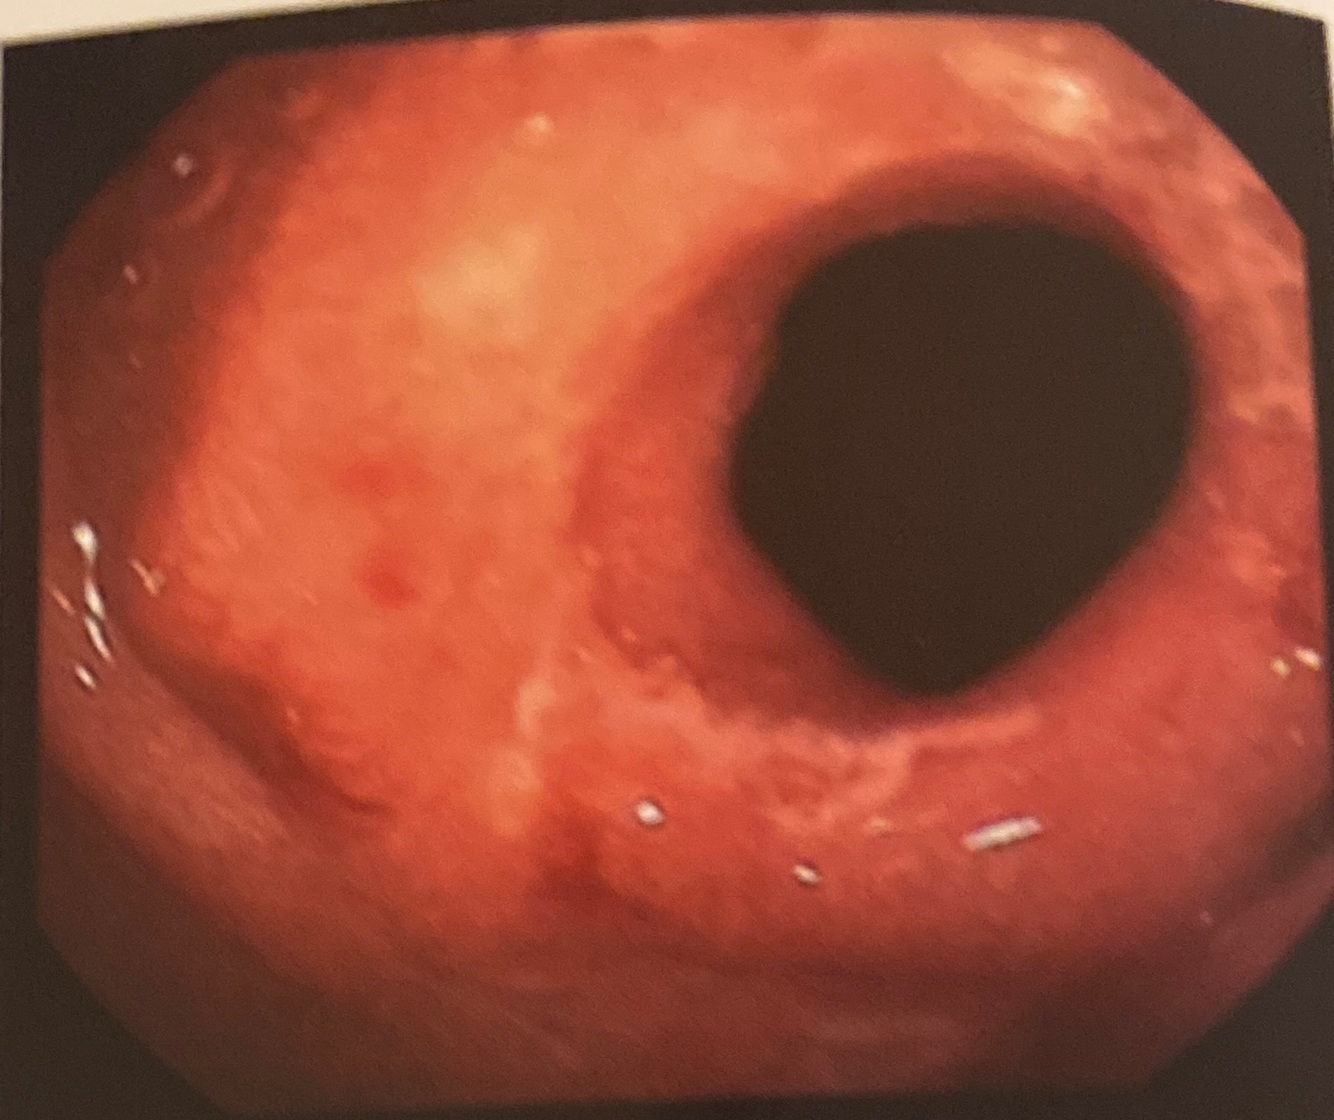

Imagem duodenal (duodenite) sugestiva de

Doença de Chron

Ulcerações irregulares, retrações cicatriciais e estenose

Ulceração linear circunferencial na segunda